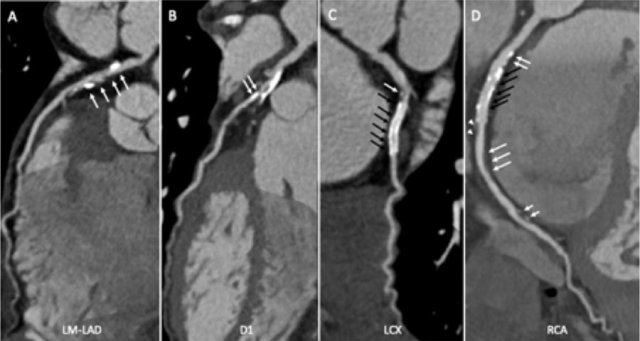

Continue with the curved MPR images of the same patient.

The findings are:

- Long, partially

calcified plaque in the LM-LAD causing moderate stenosis (50-69%) (white

arrows).

This segment of the LAD is difficult to evaluate because of blooming and step artefacts. - Calcified plaque in the D1 causing severe stenosis (70-99%) at the origin (white arrows).

- Partially calcified

plaque proximal from the LCX stent with moderate (50-69%) stenosis (white

arrow).

LCX stent patent, no stenosis (black arrows). - Calcified plaques

in the proximal RCA with minimal stenosis (<25%) (white arrows).

RCA stent patent (black arrows).

Non-calcified plaque distal to the stent causing minimal stenosis (white arrowheads).

Another non-calcified plaque in the distal RCA causing minimal stenosis (<25%) (white arrows).

Partially calcified plaque in the distal RCA with mild stenosis (25-49%) (two white half-arrows). - Total plaque burden is extensive (P4).

Due to severe stenosis in D1, extensive plaque burden, some

non-diagnostic segments and a stent this patient classifies as CAD-RADS

4A/P4/N/S, which means that this patient needs further workup.